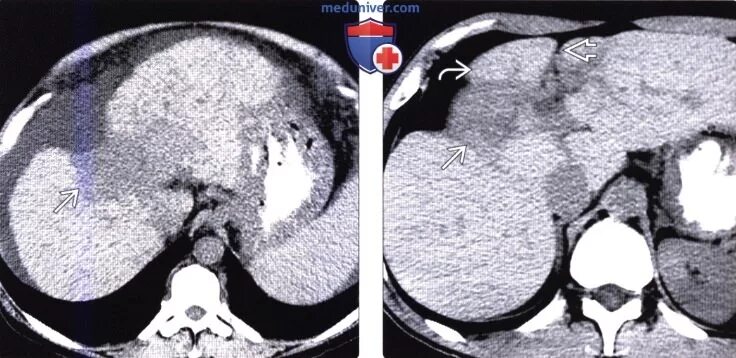

Цирроз печени кт